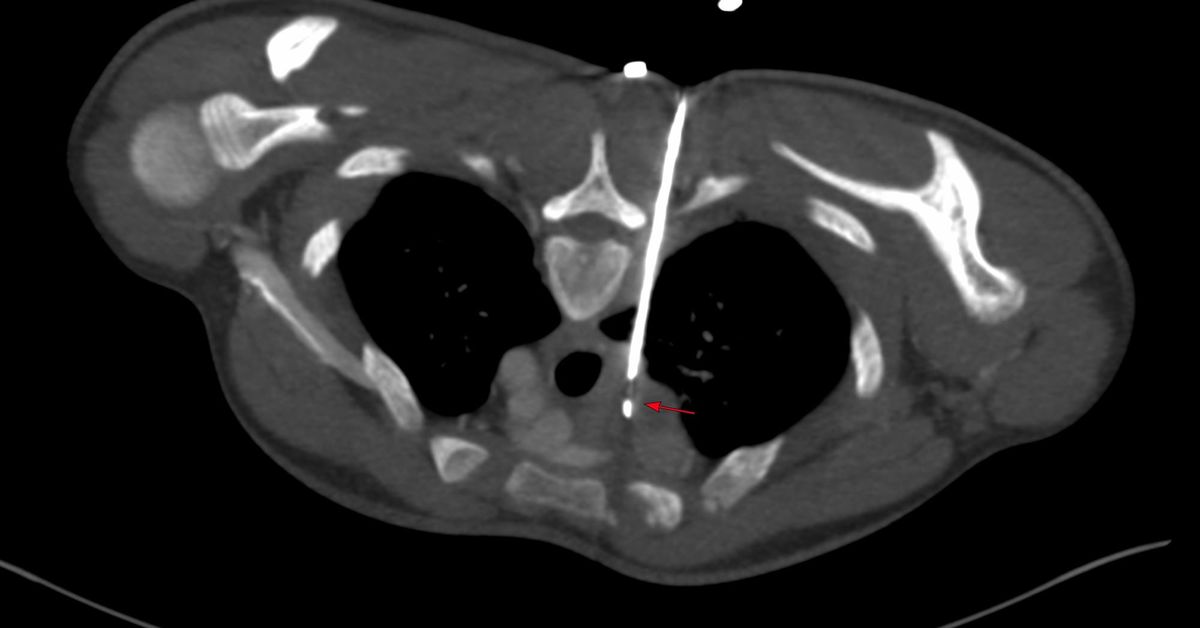

3 months later, he clinically worsened and CT scan showed the same nodes with mild increase in the subcarinal node size and bilateral effusions and he was referred for a CT guided biopsy of the subcarinal node. The short axis of the node was 25 mm, so biopsy was feasible.

The effusion was a concern, but in the prone position, the fluid moved anteriorly and did not come in the way, though a transeffusion or transpneumothorax biopsy is always a possibility.

The lung was almost at the midline and there was concern that a transparenchymal approach (A) may be needed as in the last case.

Using an 18G Cook needle, 8 cc of lignocaine was injected in the space between the pleura and foramen in the inter-transverse space (B). Once some space was created then it was advanced with 3 injections of 10-15 cc of a combination of lignocaine and saline (C, D), until the needle tip rested along the posterior margin of the node (D) and then it was pushed into the node (E) followed by the biopsy (F). The gun has a 10 mm throw.